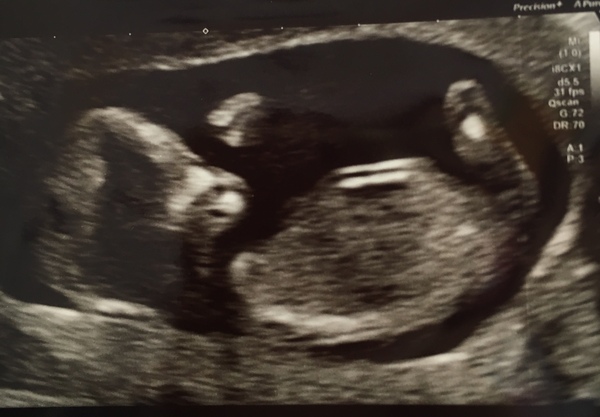

All ok with my scan thankfully, date moved forwards so due on 4th Feb - 13 weeks today!

@welshweasel beautiful picture, that's the date we got at our scan too! Though I'm kinda keeping to ivf dates unless another scan says earlier too.

@welshweasel great picture!

@welshweasel lovely picture I'm glad all went well xx

Had our scan and all the worry was for nothing thankgod.

Bean was so so wriggly having a party in there the lady Said

We got a free DVD of bean and a 4D look aswell as hearing the heart beat.

Measuring 11 weeks exactly and Edd is now 18th Feb

If anyone lives near marlow I would 1000000% recommend the baby scan studio it is amazing cannot even describe how good they are.

Very happy and we got about 8 pics :) very very happy

Second scan went well Smile although baby was a bit camera shy and not wanting to play ball kept doing somersaults all over the place! Eventually got 2 measurements.